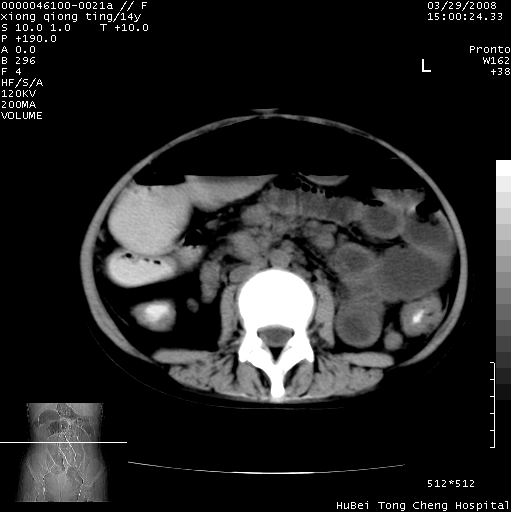

中下腹及盆腔ct轴位平扫+增强扫描(层厚10mm,螺距1.0,重建间隔10mm),图像如下:

(注:患儿检查当日上午9时口服胃肠道对比剂,下午3时许行ct扫描检查,未行对比剂直肠保留灌肠,检查当日患儿腹泻)

中下腹及盆腔ct轴位扫描(ps+ce)提示:腹部肠管明显充气扩张,并见数个不同宽度之气液平面;疑不全性肠梗阻或肠郁张。临床会诊考虑为患儿腹泻,肠郁张所致;后来未经特殊处理,患儿大便恢复正常,亦无腹胀。